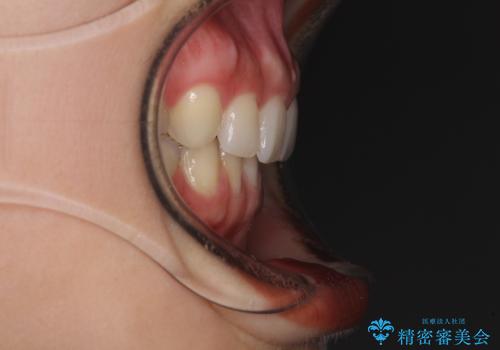

隙間だらけの歯列をきれいに インビザライン矯正とセラミック補綴治療

- 前歯の隙間と奥歯の目立つ銀歯を気にして来院された患者様です。

インビザラインにより下顎前歯の隙間を閉じるとともに、奥歯の咬み合わせを改善させることとしました。

左右奥歯の咬み合わせを変更させる必要があったため、治療期間は長くなることが予想されました。